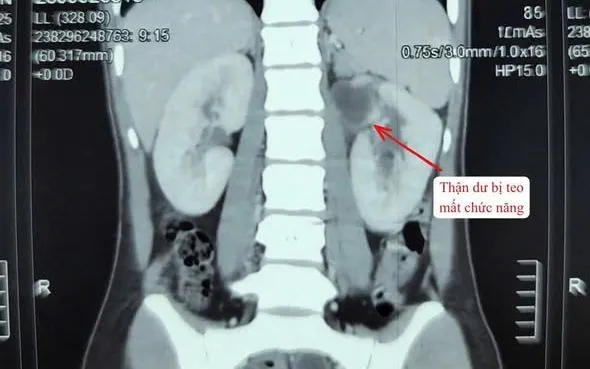

Bệnh nhân nữ 22 tuổi nhập viện trong tình trạng sốt, đau vùng hông trái. Qua thăm khám và cận lâm sàng, các bác sĩ xác định người bệnh có dị tật thận - niệu quản đôi bên trái. Trong đó, một thận đã mất chức năng, niệu quản giãn lớn, chứa nhiều mủ gây nhiễm trùng nặng.

Sau khi hội chẩn và kiểm soát tình trạng nhiễm trùng, ekip Khoa Ngoại thận tiết niệu quyết định phẫu thuật cắt bỏ toàn bộ hệ thống thận - niệu quản bên trái đã mất chức năng nhằm loại bỏ ổ nhiễm và ngăn ngừa biến chứng.